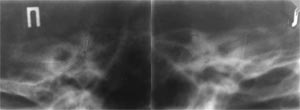

При опухолях яремного гломуса характерными признаками являются деструкция кости в области дна барабанной полости, нижней и задней поверхности пирамиды височной кости, выявляемые на рентгенограммах в проекциях Шуллера (Рис. 2), Майера, Стенверса. КТ–признакам опухоли яремного гломуса являются: увеличение яремного отверстия, эррозия краев корти кальной пластинки в области яремной вырезки, разрушение яремной стенки барабанной полости [2]. При значительной распространенности опухоли выявляются признаки разрушения в области пирамиды височной кости и прилегающих структур затылочной кости — очертаний мыщелкового и подчелюстного каналов.

[Увеличить]

Рис. 2. Опухоль яремного гломуса. На рентгенограмме в проекции Шюллера разрушено дно барабанной полости справа.